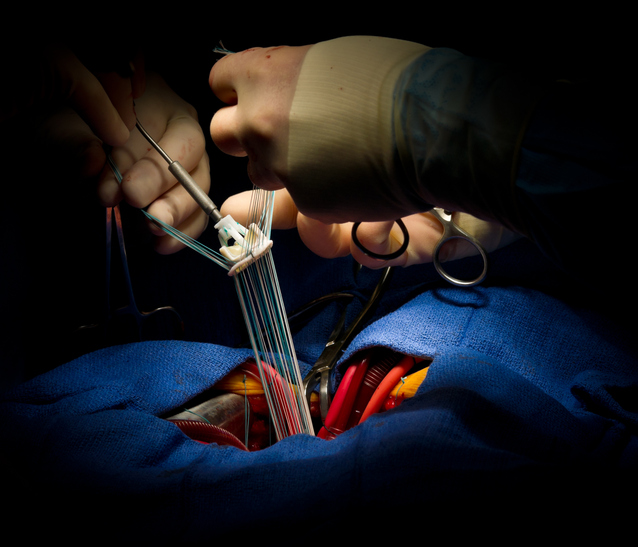

Elective mitral valve-in-valve procedures are tied to lower 3-year mortality, a large study finds.